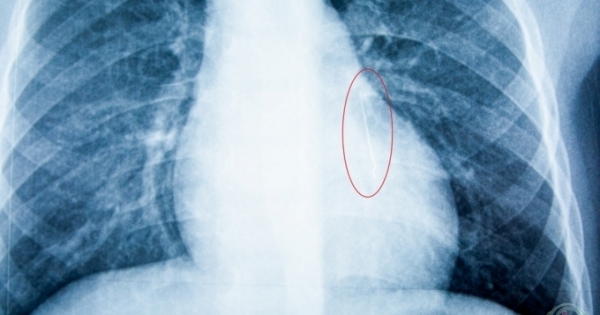

Nghệ An: Bàng hoàng phát hiện kim nhọn dài 2,5 cm trong phổi bệnh nhi 5 tuổi

Khi chụp XQuang, các bác sĩ cũng “giật mình” khi nhận thấy có đầu kim khí nhọn nằm ở vị trí 1/3 dưới phổi của bệnh nhi.